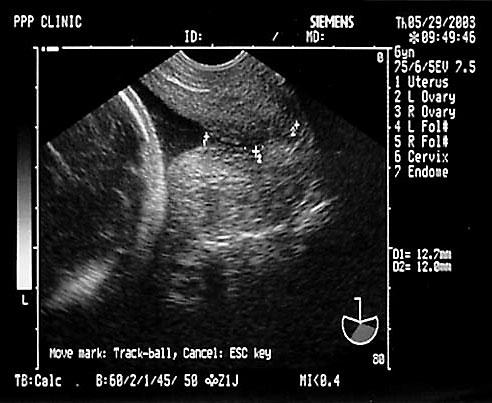

Note normal cord insertion into fetal abdomen without defect (left). Normal 3 vessel cord (right, at arrow). - Cervical Length by Transvaginal Ultrasound (TVS)

- Normal cervical length > 3 cm

Normal appearing cervix. Closed and long.

Length cervical canal

10-50 mm in 2nd and 3rd trimesters

50th% is 3.5 cm

10th% is 2.5 cm

90th% is 4.5 cm

- Cervical length < 2.5 cm at 22-24 weeks 6x increase in PTB before 35 weeks.

Shortening of cervix with mild funneling.- Often see shortening with bleeding/contractions/multiple gestation with delivery < 32 weeks

- Cervical length 1.8-2.0 cm best positive predictive value.

Marked funneling of cervix with shortening.- Cervical length 3.0 cm excludes preterm labor

- Cervical length 3.0 cm excludes preterm labor